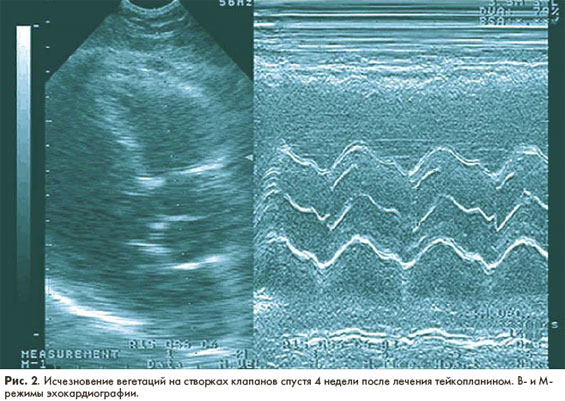

Достоверным и доступным в клинической практике критерием эффективности антибактериальной терапии ИЭ является исчезновение в ее результате вегетаций на клапанах и других структурах эндокарда при ультразвуковом исследовании сердца. На рис. 1, 2 представлены результаты ультразвукового исследования пациента (собственное наблюдение) со стрептококковым сепсисом, потверждающие высокую эффективность монотерапии тейкопланином.

результаты ультразвукового исследования  пациента со стрептококковым сепсисом